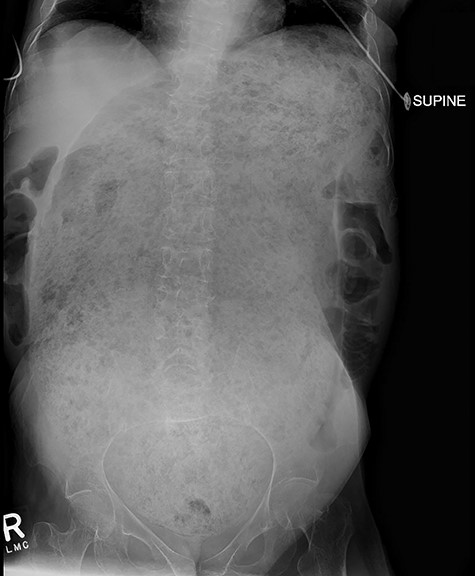

A 64-year-old female who resides in a nursing facility due to significant mental and physical disability presented to the emergency department with a 4-month history of chronic intermittent constipation. She had been treated multiple times for severe constipation and fecal impaction. On presentation, abdominal X-rays exhibited massive stool burden filling the rectum, which was distended cephalad to the diaphragm and anteriorly to the peritoneum occupying much of the abdominal cavity (Fig. 1). The patient was admitted to the hospital and aggressive bowel regimen was initiated with limited improvement. Given a history of multiple failed attempts with pharmacological therapy, surgical intervention was considered. A computed tomography scan of the abdomen showed a massive amount of stool in the rectosigmoid colon with no evidence of an obstructing lesion. The patient had undergone colonoscopy within 2 years of presentation with no evidence of polyps or malignant process. She was chronically malnourished, bedbound, non-communicative putting her at significant risk of morbidity with major intervention. Risks and benefits were discussed with the patient’s family, and it was opted for the least invasive surgical approach. We proceeded with creation of a loop colostomy of the descending colon through a mini left to midline 2.5 cm incision. The patient tolerated the procedure well. Post-operatively, she was treated with antegrade enemas through the distal limb of the colostomy as well as enemas and suppositories per rectum. Subsequent X-rays showed significant decrease in stool burden over the 14-Day period (Fig. 2). She was ultimately discharged to her nursing facility with normal bowel function.

Plain film 2 weeks post-operatively shows significant reduction in stool burden and rectal dilation.